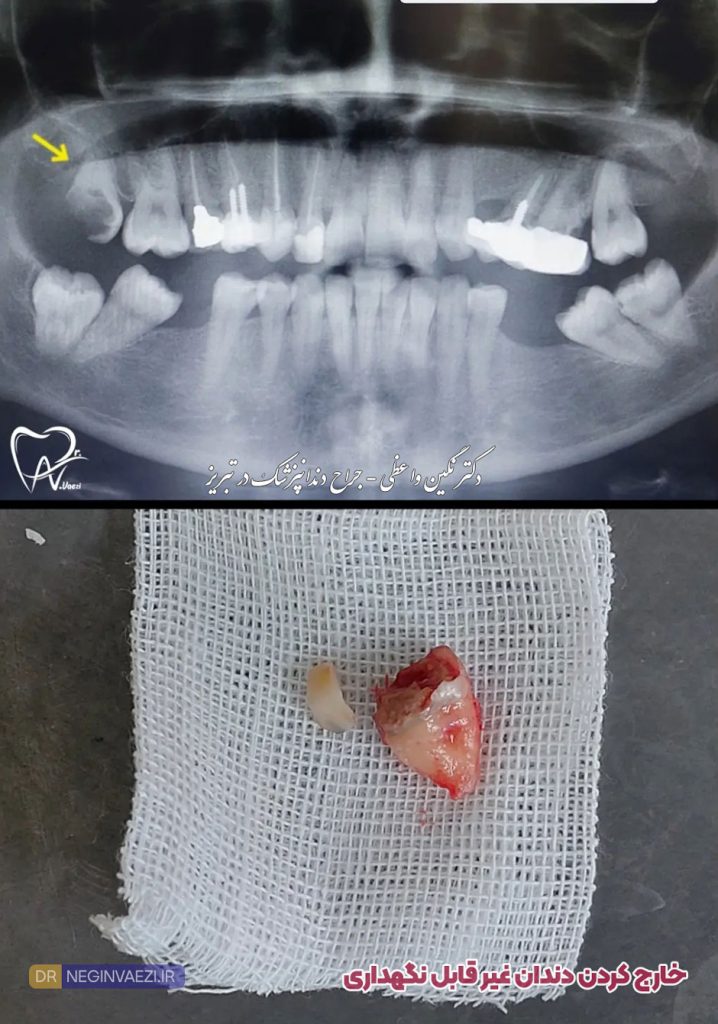

عکس جراحی دندان پوسیده و شکسته

چرا در برخی نمونه ها دندان کشیده شده چند تیکه است؟

دلایل مختلفی وجود دارد که یکی از مهمترین آنها پوسیدگی یا تخریب شدید دندان هست که هنگام خارج سازی تیکه تیکه می شود، گاهی وقت ها نیز، خود دندانپزشک جهت سهولت در خارج شدن و جلوگیری از خرد شدن دندان، آن را چند تیکه می کند تا خارج سازی آن راحتتر انجام شود.

عکس جراحی دندان شکسته